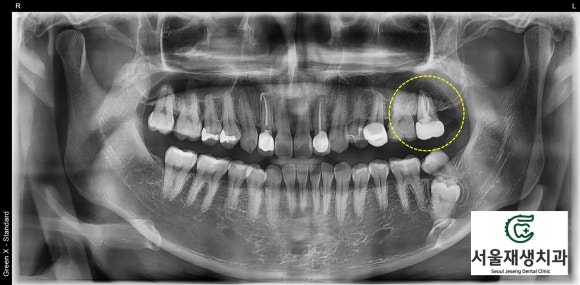

![[재신경치료] 예전에 신경치료 한 치아가 갑자기 붓고 아파요! (현미경 신경치료, 서울재생치과) 관련 이미지 5](https://pub-9f2bb3498faf4d1d8714b41df24753e3.r2.dev/content/clinics/archive/nqmm0udu86/naver_blog/honeybeevuvu/assets/by_hash/276a3eb18024b1408ac1f8f44336f5e0019d3700c9f9253de6861b919e85f318.jpg)

치과 검사의 가장 기본이 되는

파노라마 엑스레이입니다.

사진상으로 오른쪽 꼭대기에

심상치 않은 치아가 관찰됩니다.

한 달 반정도 되었을 때...

뿌리 끝의 염증의 크기가 확연히 감소한 것처럼 보입니다.

CT를 찍어서 정확히 비교해봅니다.

![[재신경치료] 예전에 신경치료 한 치아가 갑자기 붓고 아파요! (현미경 신경치료, 서울재생치과) 관련 이미지 11](https://pub-9f2bb3498faf4d1d8714b41df24753e3.r2.dev/content/clinics/archive/nqmm0udu86/naver_blog/honeybeevuvu/assets/by_hash/324407aacfed1bafe57094f5fc6f937d9f4f911d2993cc554309502f9abbd525.jpg)

뿌리를 타고 상악동까지 넘어가 있던

염증이 모두 사라졌습니다.

심지어 뿌리 주위로 새로운 골이 자라들어오는 소견입니다.

한 달 반만의 일입니다.

이렇게까지 빨리 아물길 바란 건 아니었는데....

무서운 회복력을 가지신 환자분입니다.